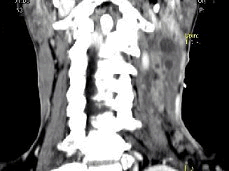

男,67岁,口咽部异物感约8个月,伴口咽部疼痛,患者无明显发热。如图所示最可能的诊断为()

A.扁桃体结核伴淋巴结转移

B.扁桃体脓肿伴淋巴结转移

C.扁桃体癌伴淋巴结转移

D.扁桃体淋巴瘤

E.下咽癌伴淋巴结转移

[单选题,A1型题] 男,67岁,口咽部异物感约8个月,伴口咽部疼痛,患者无明显发热。如图所示最可能的诊断为()A . 扁桃体结核伴淋巴结转移B . 扁桃体脓肿伴淋巴结转移C . 扁桃体癌伴淋巴结转移D . 扁桃体淋巴瘤E . 下咽癌伴淋巴结转移